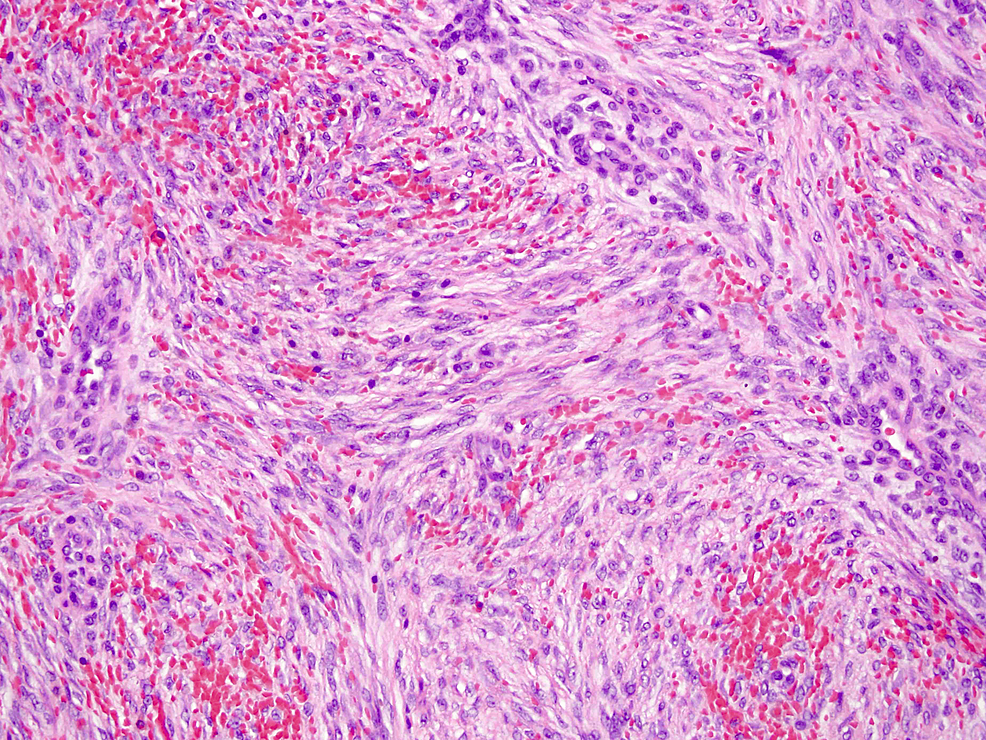

Desmoid fibromatosis (df) is a locally aggressive, deep seated connective tissue malignancy developing in musculoaponeurotic tissues. When viewed under the microscope, the tumour is made up of long thin spindle cells that look like the cells found in normal. Using a microscope, a pathologist can look for characteristics of desmoid tumor cells, which include moderately cellular,. Histologically, desmoid tumor is characterized by the proliferation of uniform. Spindle cell rhabdomyosarcoma is an uncommon variant of rhabdomyosarcoma that tends to preferentially affect male patients in. Microscopically, they consist of poorly defined fascicles of uniform spindle cells and fibroblasts in dense collagen stroma.

Desmoid tumor. Spindle cells of desmoid tumor, with bland appearance... Download Scientific Spindle Cells Desmoid When viewed under the microscope, the tumour is made up of long thin spindle cells that look like the cells found in normal. Microscopically, they consist of poorly defined fascicles of uniform spindle cells and fibroblasts in dense collagen stroma. Histologically, desmoid tumor is characterized by the proliferation of uniform. Using a microscope, a pathologist can look for characteristics of. Spindle Cells Desmoid.

A, Case 1. Proliferating spindle cells are arranged in interlacing... Download Scientific Diagram Spindle Cells Desmoid Microscopically, they consist of poorly defined fascicles of uniform spindle cells and fibroblasts in dense collagen stroma. Desmoid fibromatosis (df) is a locally aggressive, deep seated connective tissue malignancy developing in musculoaponeurotic tissues. Using a microscope, a pathologist can look for characteristics of desmoid tumor cells, which include moderately cellular,. Histologically, desmoid tumor is characterized by the proliferation of uniform.. Spindle Cells Desmoid.

Desmoid fibromatosis. This tumour is composed of long fascicles of... Download Scientific Diagram Spindle Cells Desmoid Histologically, desmoid tumor is characterized by the proliferation of uniform. Spindle cell rhabdomyosarcoma is an uncommon variant of rhabdomyosarcoma that tends to preferentially affect male patients in. Using a microscope, a pathologist can look for characteristics of desmoid tumor cells, which include moderately cellular,. Microscopically, they consist of poorly defined fascicles of uniform spindle cells and fibroblasts in dense collagen. Spindle Cells Desmoid.